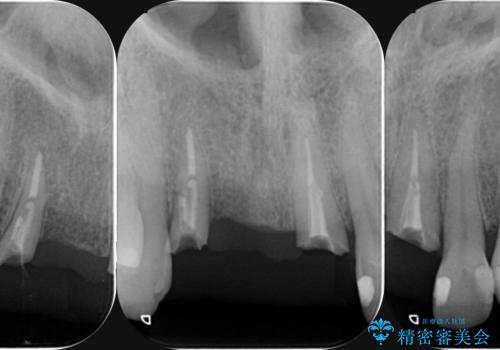

前歯が折れた 前歯部審美セラミックブリッジ治療

- ブリッジの根元が折れ、審美性の改善・治療を求めて来院されました。

保存の難しい歯を抜去しロングブリッジによる補綴を選択しました。

かみ合わせの観点からインプラント治療は難しく、入れ歯も希望されなかったためブリッジによる補綴を選択しました。